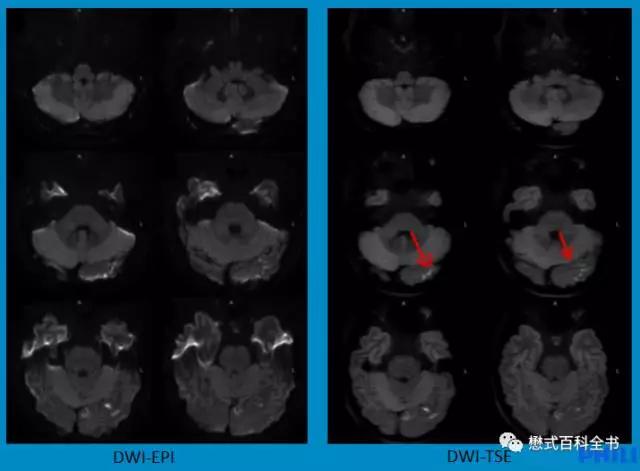

飞利浦公司创新的DWI-TSE序列是一个突破性的改进。我们知道DWI序列一般是采用EPI采集的,结合了EPI采集。而飞利浦可以使用TSE(快速自旋回波)序列做成DWI序列。

TSE序列,由于有多个180°脉冲重聚,所以图像变形小,对磁敏感伪影不敏感。

图18:传统的DWI-EPI弥散序列 vs 飞利浦创新的DWI-TSE弥散序列

由于采用了TSE读出,所以图像变形非常小,而且对磁化率伪影不敏感。

这样的最大优势是用在磁化率敏感区,比如:桥小脑三角区,颈部等部位。

传统上,由于这些部位含有大量气体,导致磁敏感加剧,普通弥散序列变形大,伪影大,根本无法满足临床诊断;而使用飞利浦的DWI-TSE则可以轻松搞定这些部位。

图19-21:DWI-TSE序列减少弥散图像变形,消除磁敏感伪影,对桥小脑三角区和颈部弥散有非常实用的临床意义